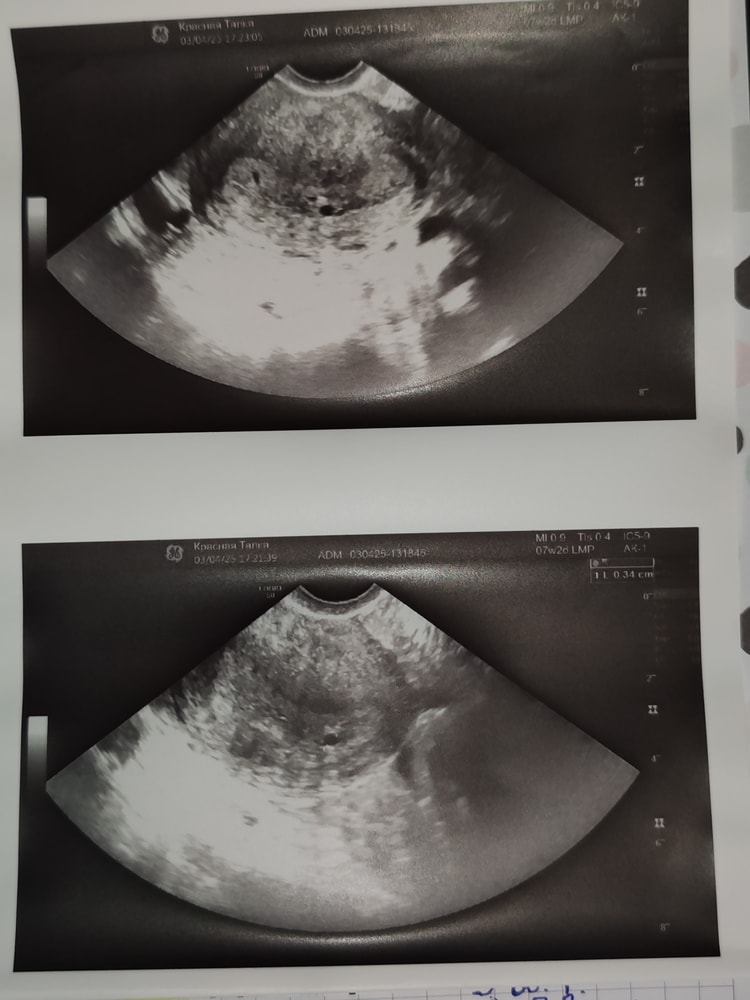

03.04 третий анализ крови на ХГЧ 745,70. На УЗИ вроде нашли плодное яйцо 2-3 недели, но сказали что не нашли жёлтое тело и возможно сохранить беременность не получится, но сказали пить дюфастон по одной таблетке каждые 8 часов, что я и сделала.

07.04 четвёртый анализ крови на ХГЧ 1099. Пошла на УЗИ в другую клинику. Врач проигнорировал плодное яйцо в полости матки, сказав что оно может быть ложным. Жёлтое тело нашёл на правом яичнике, но сказал что возможно у меня эктопическая интерстициальная беременность, то есть внематочная, которая находится в трубе на стыке с маткой. Ещё что-то говорил о эхогенных образованиях в матке. Честно говоря я ему не верю от слова совсем и на это есть несколько причин. Во первых он очень долго меня мучил на этом узи, я лежала на кушетке около 15ти минут, как будто бы искал к чему придраться. Да и к тому же моментом так сильно надавил, что мне стало больно. Во вторых, мне на первом узи четко показали плодное яйцо, которое примерно соответствует тому сроку, который я посчитала ориентируюсь на цикл и тесты на ЛГ. И в третьих у меня ничего не болит, ХГЧ растёт, хоть и не так быстро, но и не прям медленно, да и кровянистых у меня нет и не было.

P. S. Приложила фото тестов и снимок с первого узи